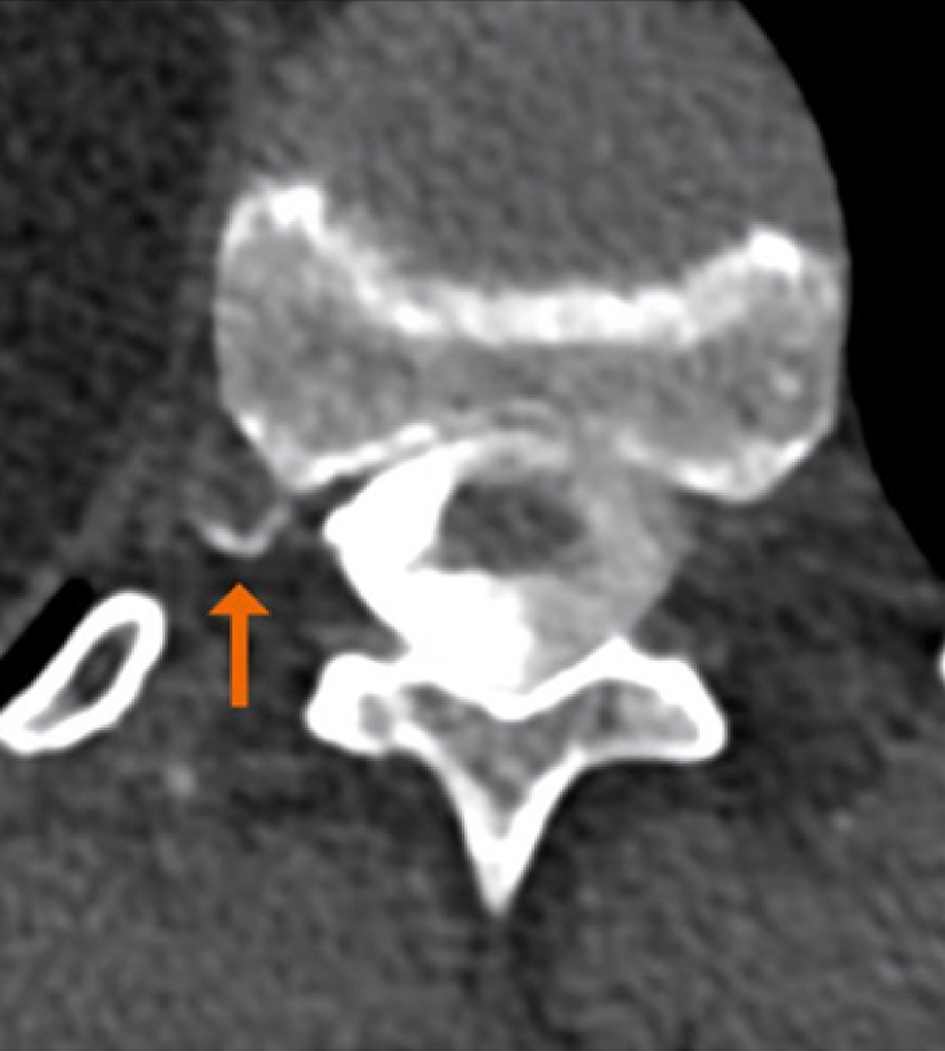

Figure 4 On the lumbar spine images acquired on the photon-counting computed tomography (on the left), the metallic artifacts are less evident when compared with conventional computed tomography (on the right).